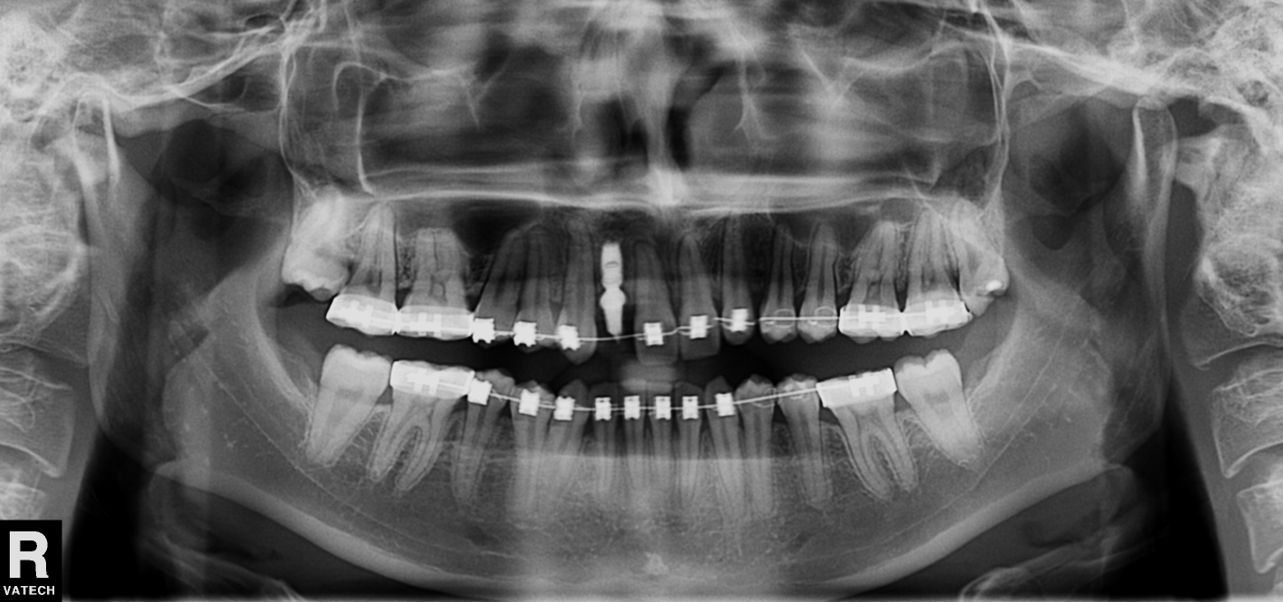

私は、前歯が2本先天的に欠損している症例について発表しようかと思っています。歯の本数が少ないので、全体的に歯が空いてきていたので矯正で位置をそろえてから、インプラントを入れました。レントゲンではこんな感じです。

本当は2本足りないので2本入れたかったのですが、2本入れるスペースを作ろうとすると少し前歯が出た感じになりそうでしたので敢えて1本にしました。左右で非対称になりがちですが、なんとか目立たない程度に収めたようになりました。こんな感じで、学会のように堅苦しくない雰囲気のものですので、もしもご興味がある先生方は、ぜひともご参加いただければと思います。懇親会はふぐ料理が格安で食べれるという企画もありますので、お気軽に参加してください。